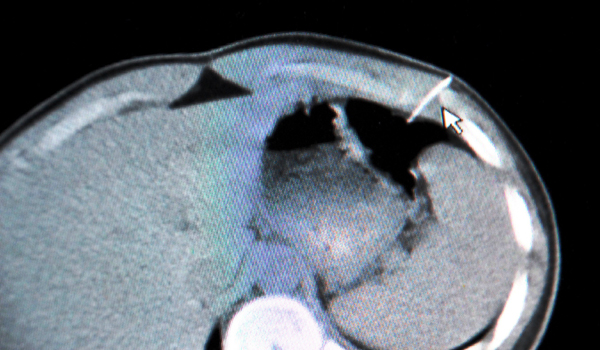

KSÜ TIP FAKÜLTESİ BİR İLKE DAHA İMZA ATTI

12 GÜN SONRA HAYATA DÖNDÜ

İLİMİZDE İLK DEFA YANIKLI HASTAYA DERİ GREFTİ UYGULAMASI BAŞARIYLA GERÇEKLEŞTİRİLMİŞTİR.